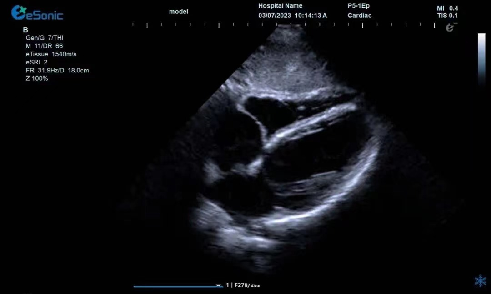

临床病例(一)

女性,68岁,临床诊断:冠心病

超声表现:左房大,左室壁运动幅度明显减低,以室间隔较明显;心包腔内见无回声区,右室前壁8mm,左室侧壁10mm。

冠心病、心包积液

临床病例(二)

男性,82岁,临床诊断:风心病 房颤

超声表现:左房大,二尖瓣增厚、回声增强、运动僵硬;CDFI显示二尖瓣、三尖瓣、主动脉瓣返流信号。

风心瓣膜病二、三尖瓣关闭不全

临床病例(三)

二尖瓣病变,脱垂?三叶?